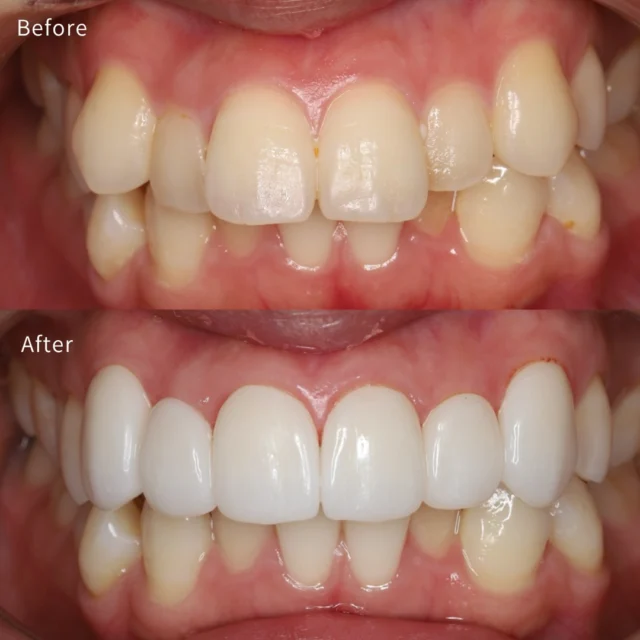

美容歯科・審美歯科というと見た目の美しさのみをイメージしがちですが、歯を1本でも多く残せるような口腔内の機能的・健康的な観点も考慮した治療を日々行なっております。

インビザライン矯正において全国1%未満のライセンスであるダイヤモンドプロバイダーを保持しており、圧倒的な症例実績と経験に基づき審美性、機能性を両立させた理想的な歯並びの実現に取り組んでいます。

歯科治療はドクターと患者さん、双方が納得した上で進めていくべきであると考えてる私は、患者さんの声に真摯に耳を傾け、一人ひとりに寄り添った適切な治療計画を提供をします。

セラミック治療やマウスピース矯正のメリットだけを強調するのではなく、10年、20年先を見据えて美しい歯を保つためのご提案をいたします。